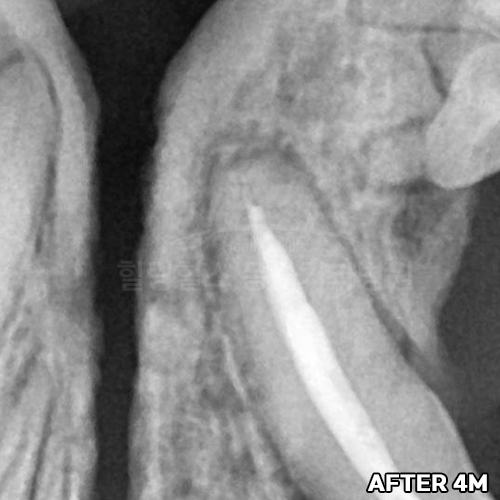

[신경치료 4개월 후 사라진 치근단농양!!]

샘플